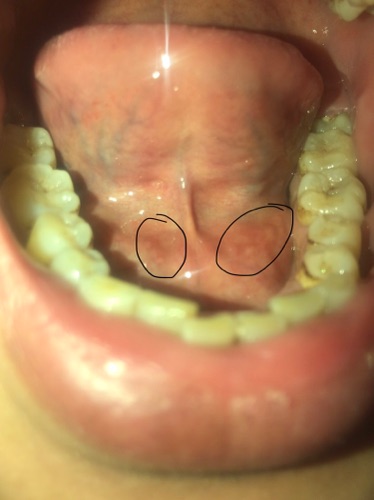

E bị nổi cục dưới niêm mạng miêng vs họng ntn phai 1 năm rồi là bị sao ạ tiểu sử e bị viêm họng ho và bị trào ngược dạ dầy

Sờ tay vào dưới niêm mac miẹng co 2 cục to nhu dau đũa ấn v cứng

Ko đau